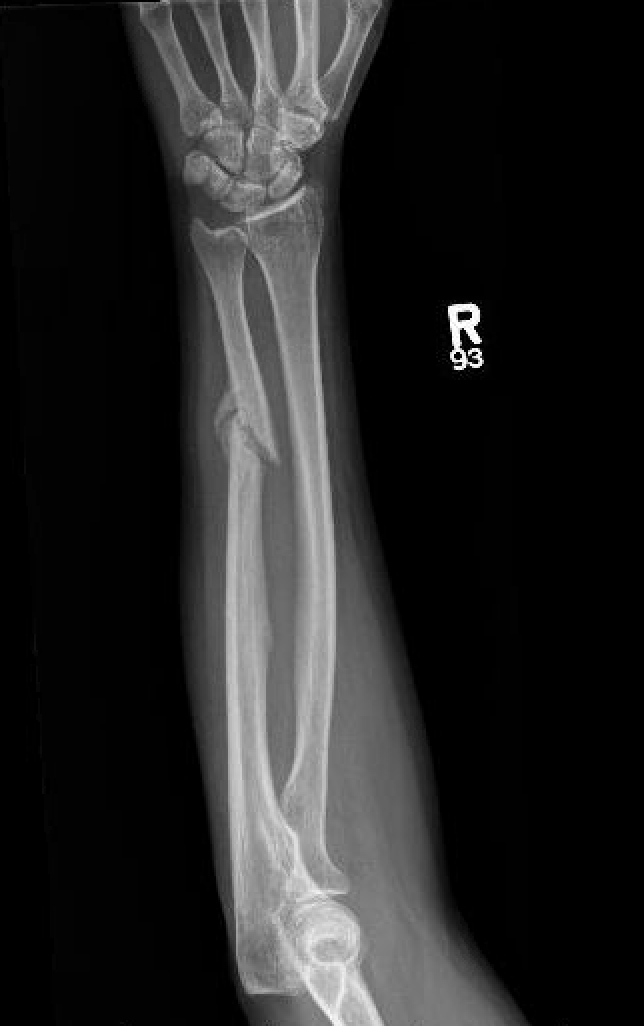

Mechanism

Night stick injury - direct blow or trauma to ulna

Location

Distal 1/3

Midshaft / middle 1/3

Proximal - beware Monteggia / radial head dislocation